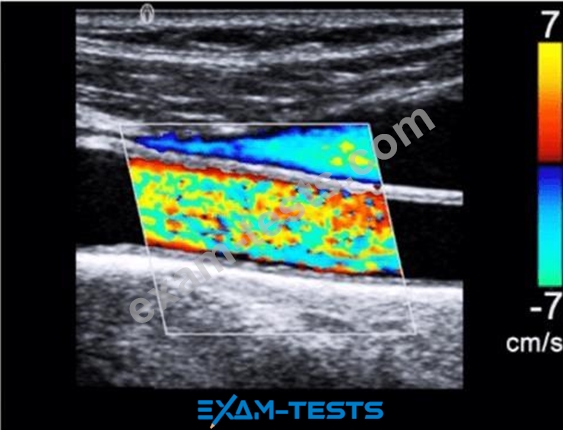

What adjustment is needed to optimize the color in the image below?